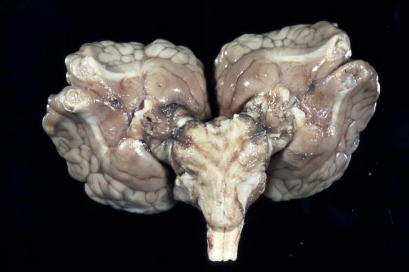

What is this condition in a cat?

Lissencephaly